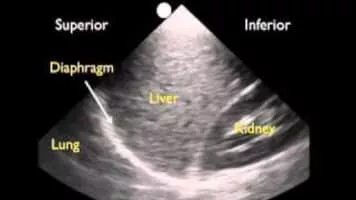

Chest Sonography photograph

Chest Sonography

Chest sonography is an established procedure in the stepwise imaging diagnosis of pulmonary and pleural disease. It is the method of choice to distinguish between solid and liquid lesions and allows the investigator to make an unequivocal diagnosis without exposing the patient to costly and stressful procedures. . . .